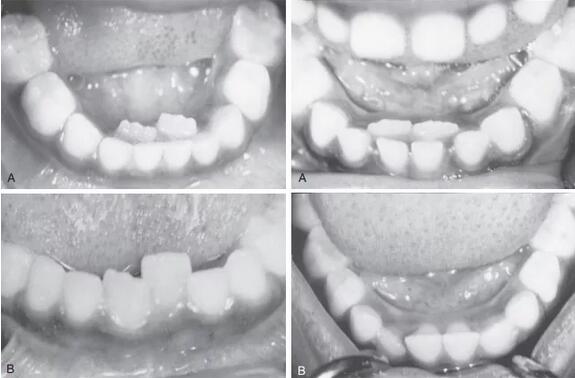

但是在儿科口腔学权威著作《McDonald and Avery’s dentistry for the child and adolescent》[5]里,却否定了这点,提到在牙弓长度明显不足的患者和主切牙间距适当的患者中都可以看到,如下图所示。

图片来自参考文献[5]

左图A提示牙弓较短,右图A提示正常,但都有双排牙。

并且在这两种情况下,几个月后恒牙位置都能得到改善,如上图中B所示(右图B是拔出了滞留乳牙),这和舌头和持续的牙槽骨生长有关。